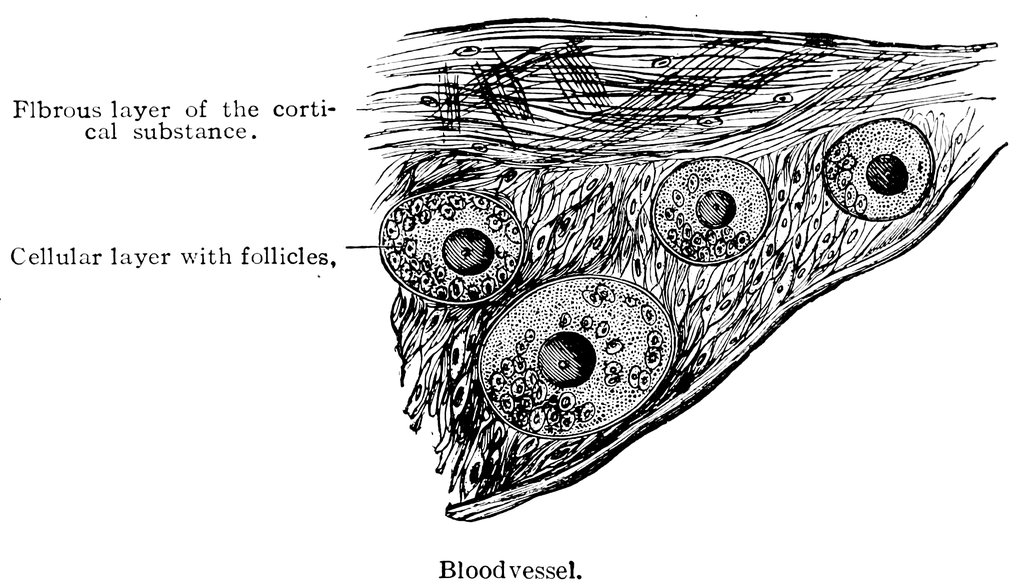

| 16. | Ripening follicles | 61 |

We must first consider the changes in the ovaries, which play an etiologically important part. At the onset of puberty, the follicular masses of the ovary exhibit a more active growth, the follicles increase in size, with their contained ova they approach the surface, and finally, by the bursting of the follicles, the ova are extruded. Then, in the life-phase in which conception occurs, and under the influence of the hyperæmia of all the pelvic viscera that accompanies this process, a notable development of the corpus luteum takes place, this latter body reaching its maximum size in the eleventh week of pregnancy, subsequently undergoing involution and leading to the formation of a considerable scar. Finally, in the critical period of life in which the menstrual flow ceases, a continually increasing growth and new formation of connective tissue-stroma takes place in the ovaries at the expense of their cellular constituents, and a regressive metamorphosis of the graafian follicles occurs.

In association with these sexual processes there ensues a series of striking changes in the shape and consistency of the ovaries, affecting both the surface and the parenchyma of these organs, and capable of stimulating the nervous ramifications in their tissue. In this connection it is worthy of note that the branches supplying the ovaries from the spermatic plexuses of the sympathetic contain a considerable proportion of sensory fibres.